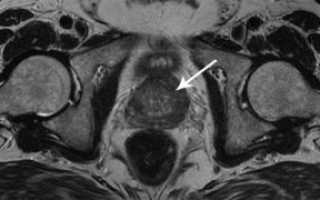

При раке простаты на МРТ-снимке визуализируются плотные скопления, которые отсутствуют при здоровом органе.

В ходе сканирования появляется возможность выявления формы онкологии. Например, слабый резонанс «говорит» о развитии опухоли, образованной клетками с муцином.

Для определения характера опухоли (злокачественной или доброкачественной) проводится биопсия.

МРТ снимок простаты (рак)